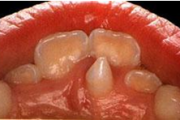

Lutipudelikaariese kahjustused

Lutipudelikaaries